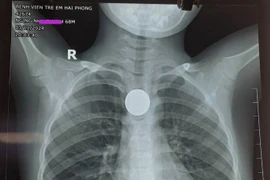

Gắp đồng xu máy trò chơi trong thực quản bé gái 3 tuổi

Theo lời kể của gia đình, 13h chiều cùng ngày, cháu N chơi ở nhà và nuốt phải đồng xu của máy trò chơi nên được gia đình đưa đến Bệnh viện.